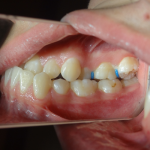

Mordida Lateral

El caso muestra un manejo de primera fase con ortopedia en un niño con el objetivo de descruzar la mordida lateral y restablecer la función normal al deglutir y fono articular, antes de llegar al pick de crecimiento. Más adelante se hará una segunda fase ortodòncica para terminar la oclusión dentaria.